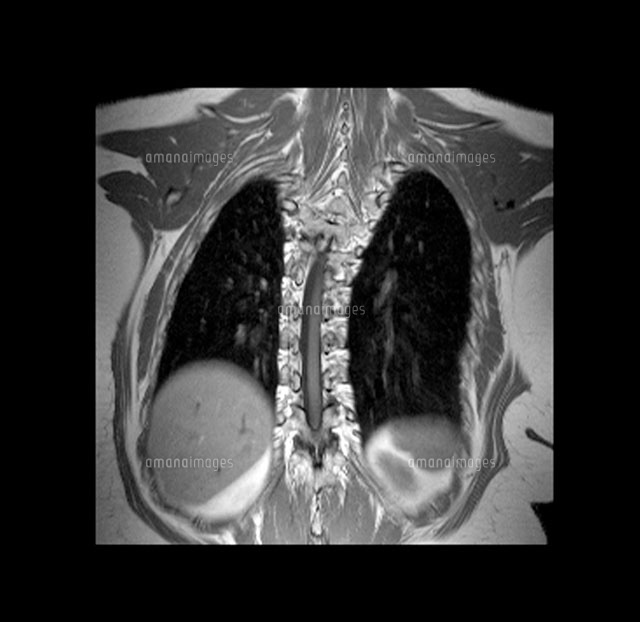

側 弯症 イラスト

側 弯症 イラストのギャラリー